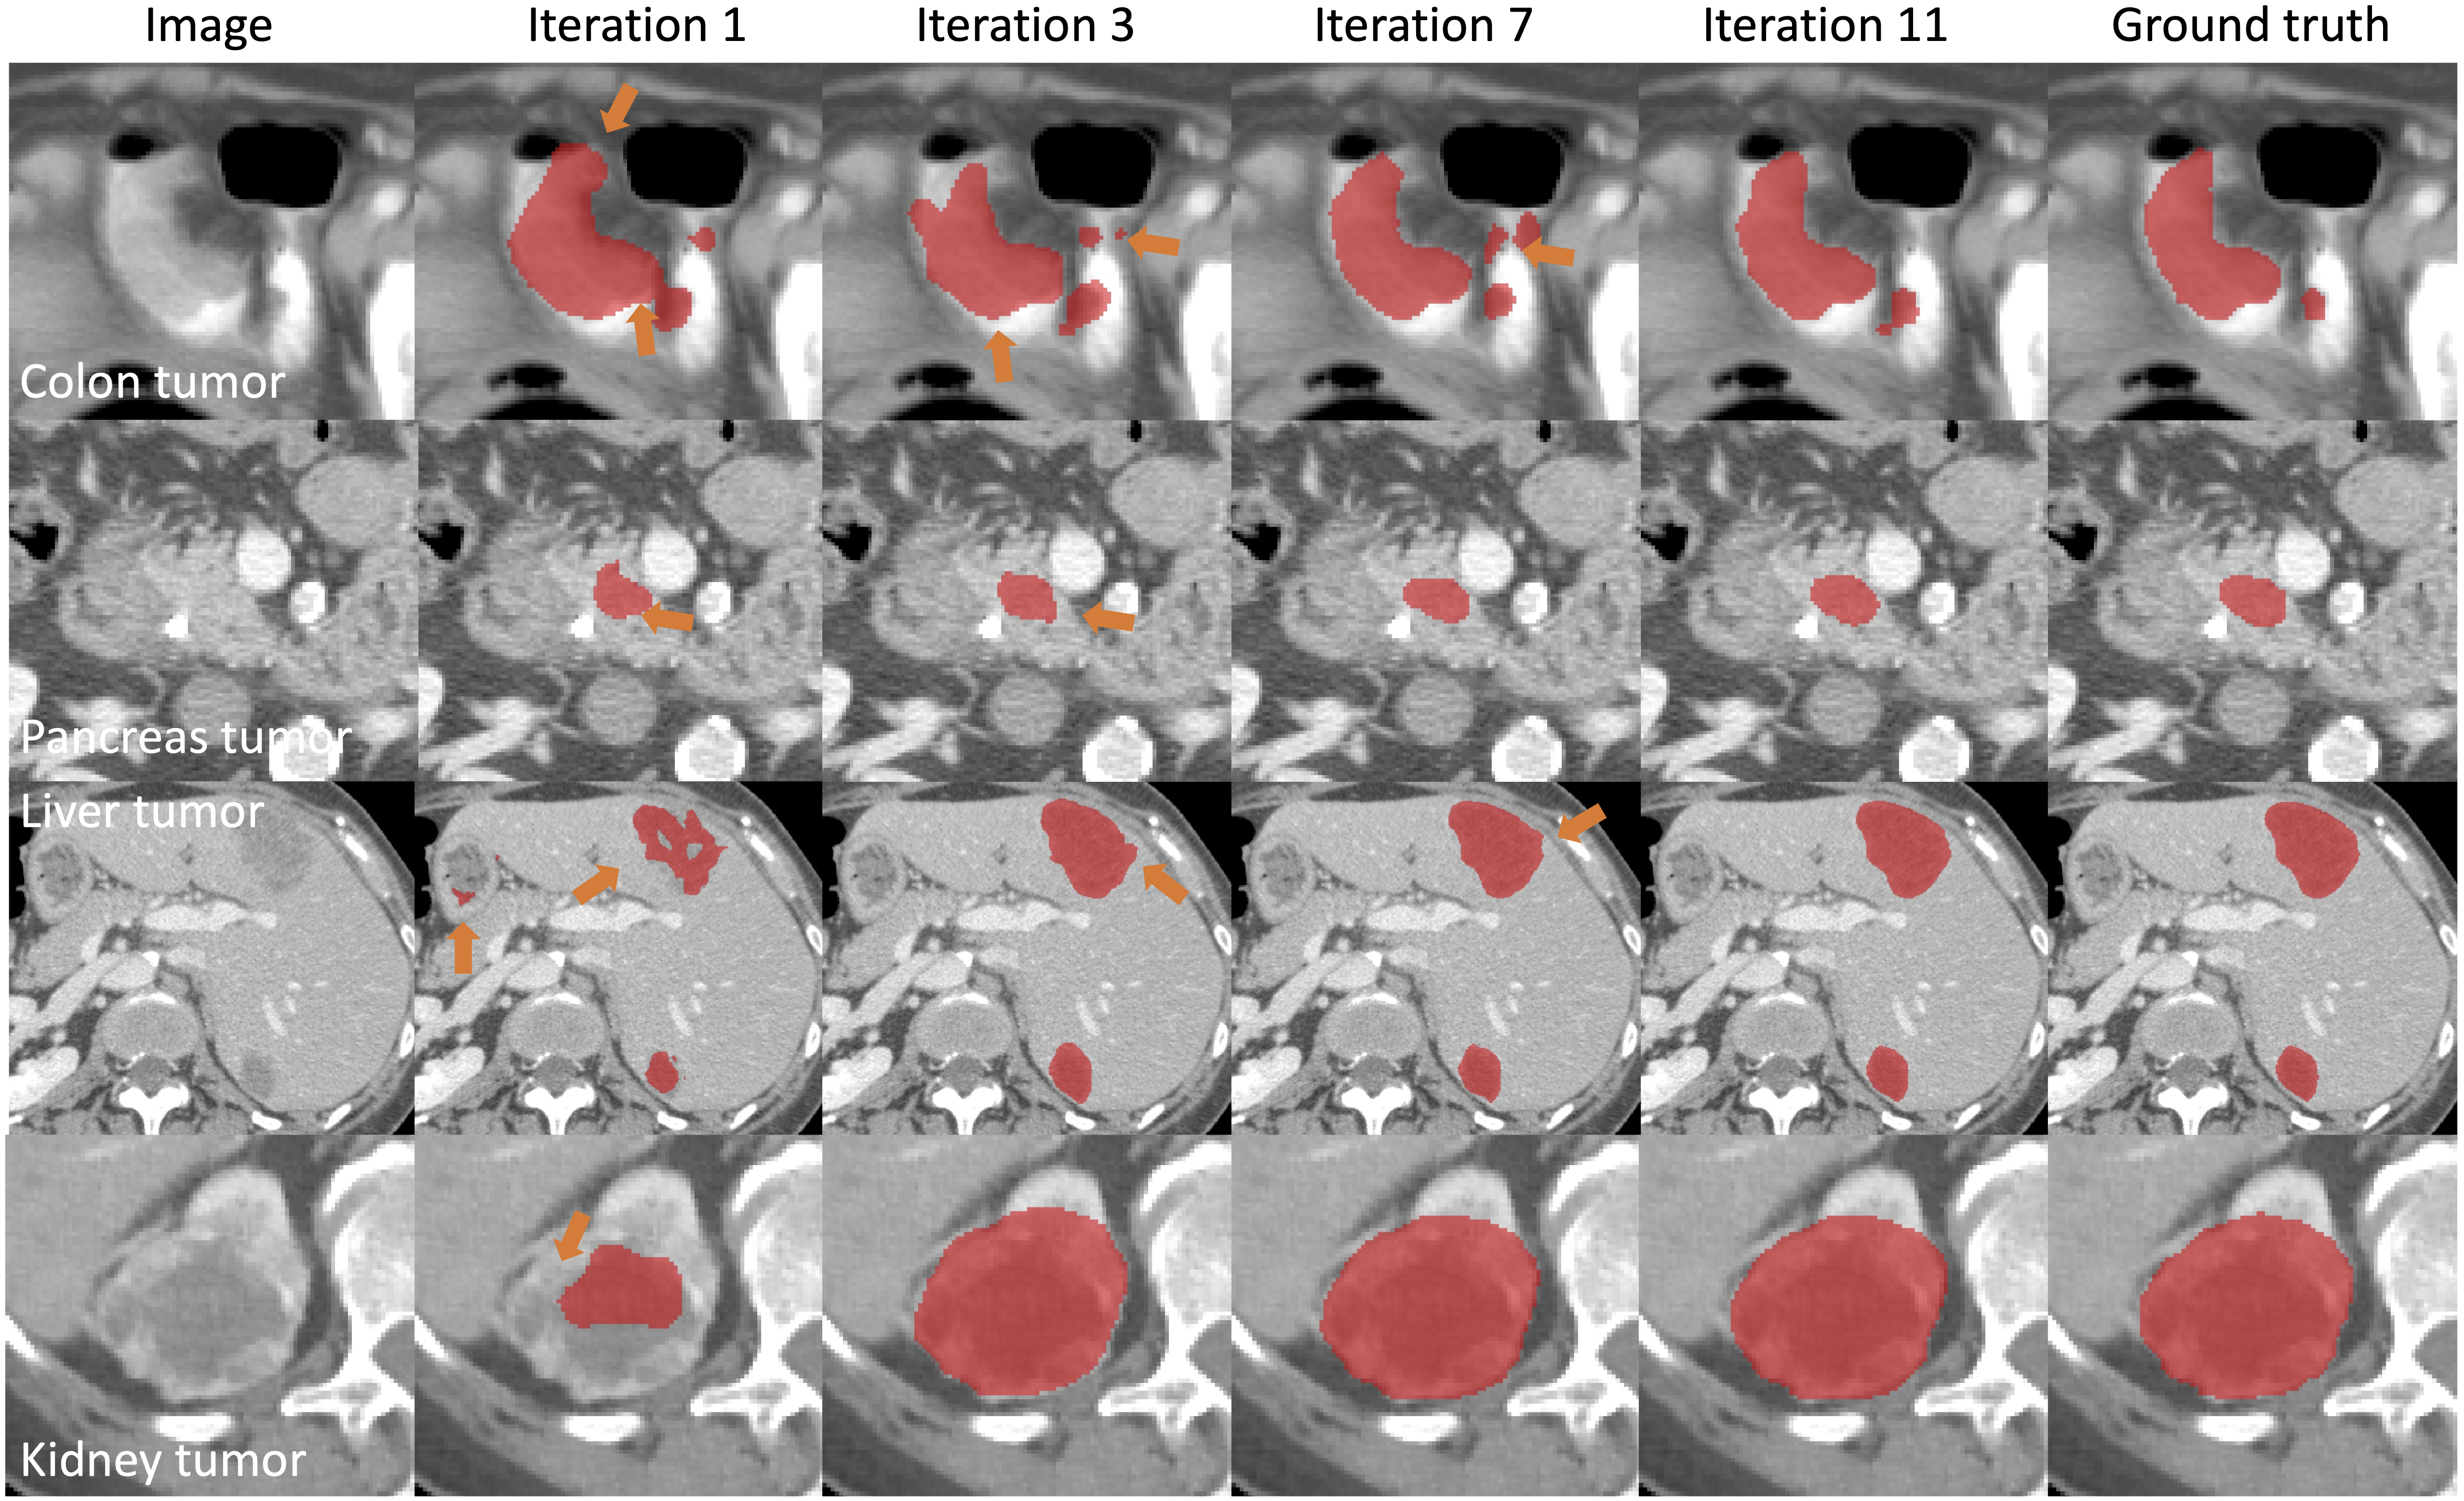

PRISM tumor segmentation examples

Briefly, PRISM produces tumor segmentation with mean Dice values of 93.79 (colon), 94.48 (pancreas), 94.18 (liver), and 96.58 (kidney).

Iterative correction for colon tumor iterative_colon

Iterative correction for multiple tumors iterative_all